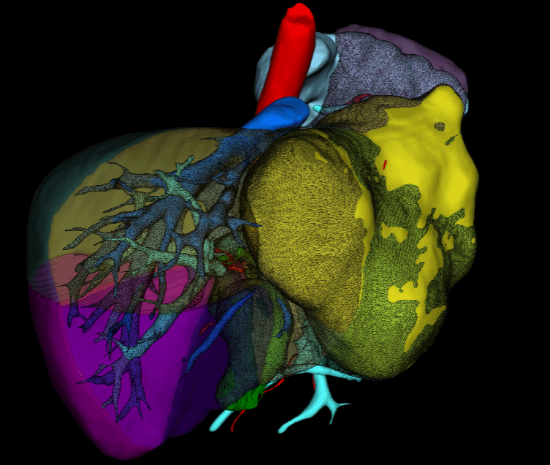

抗休克同时,蒋安主任医师团队完善必要的术前检查:患者 Child A 级肝功,ICGR15 <10。经肝脏三维重建模拟计算后发现:肝肿瘤体积约为 888.6 cm3,拟切除包含肝中静脉的扩大左半肝体积为 1096.3 cm3,,残肝体积 1306.6 cm3,,标准肝体积 1374.1 cm3,,残肝比达到 95%(图 3、图 4)。经过与曲凯副主任科室讨论后认为,残余肝脏满足安全需求,在患者条件满足一期手术的情况下急诊切除肿瘤,较介入止血更为直接。决定为患者实施切除肝左、肝中静脉的扩大左半肝切除术。